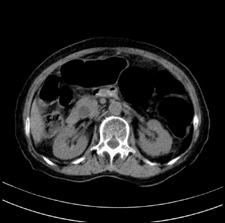

患者,女,75岁。腹痛,体黄5日,膝胸位时腹痛缓解。肝功能明日出来。彩超提示胆总管占位,未见血流信号。心电图提示s-t段改变。患者体质较弱,未能增强。

胆总管上段,腔内有软组织密度影 ,ct值36-44hu。大家看有没有胆管癌的可能。

胆管没有鼠尾征,还是考虑结石

胆管结石并发胆管炎。